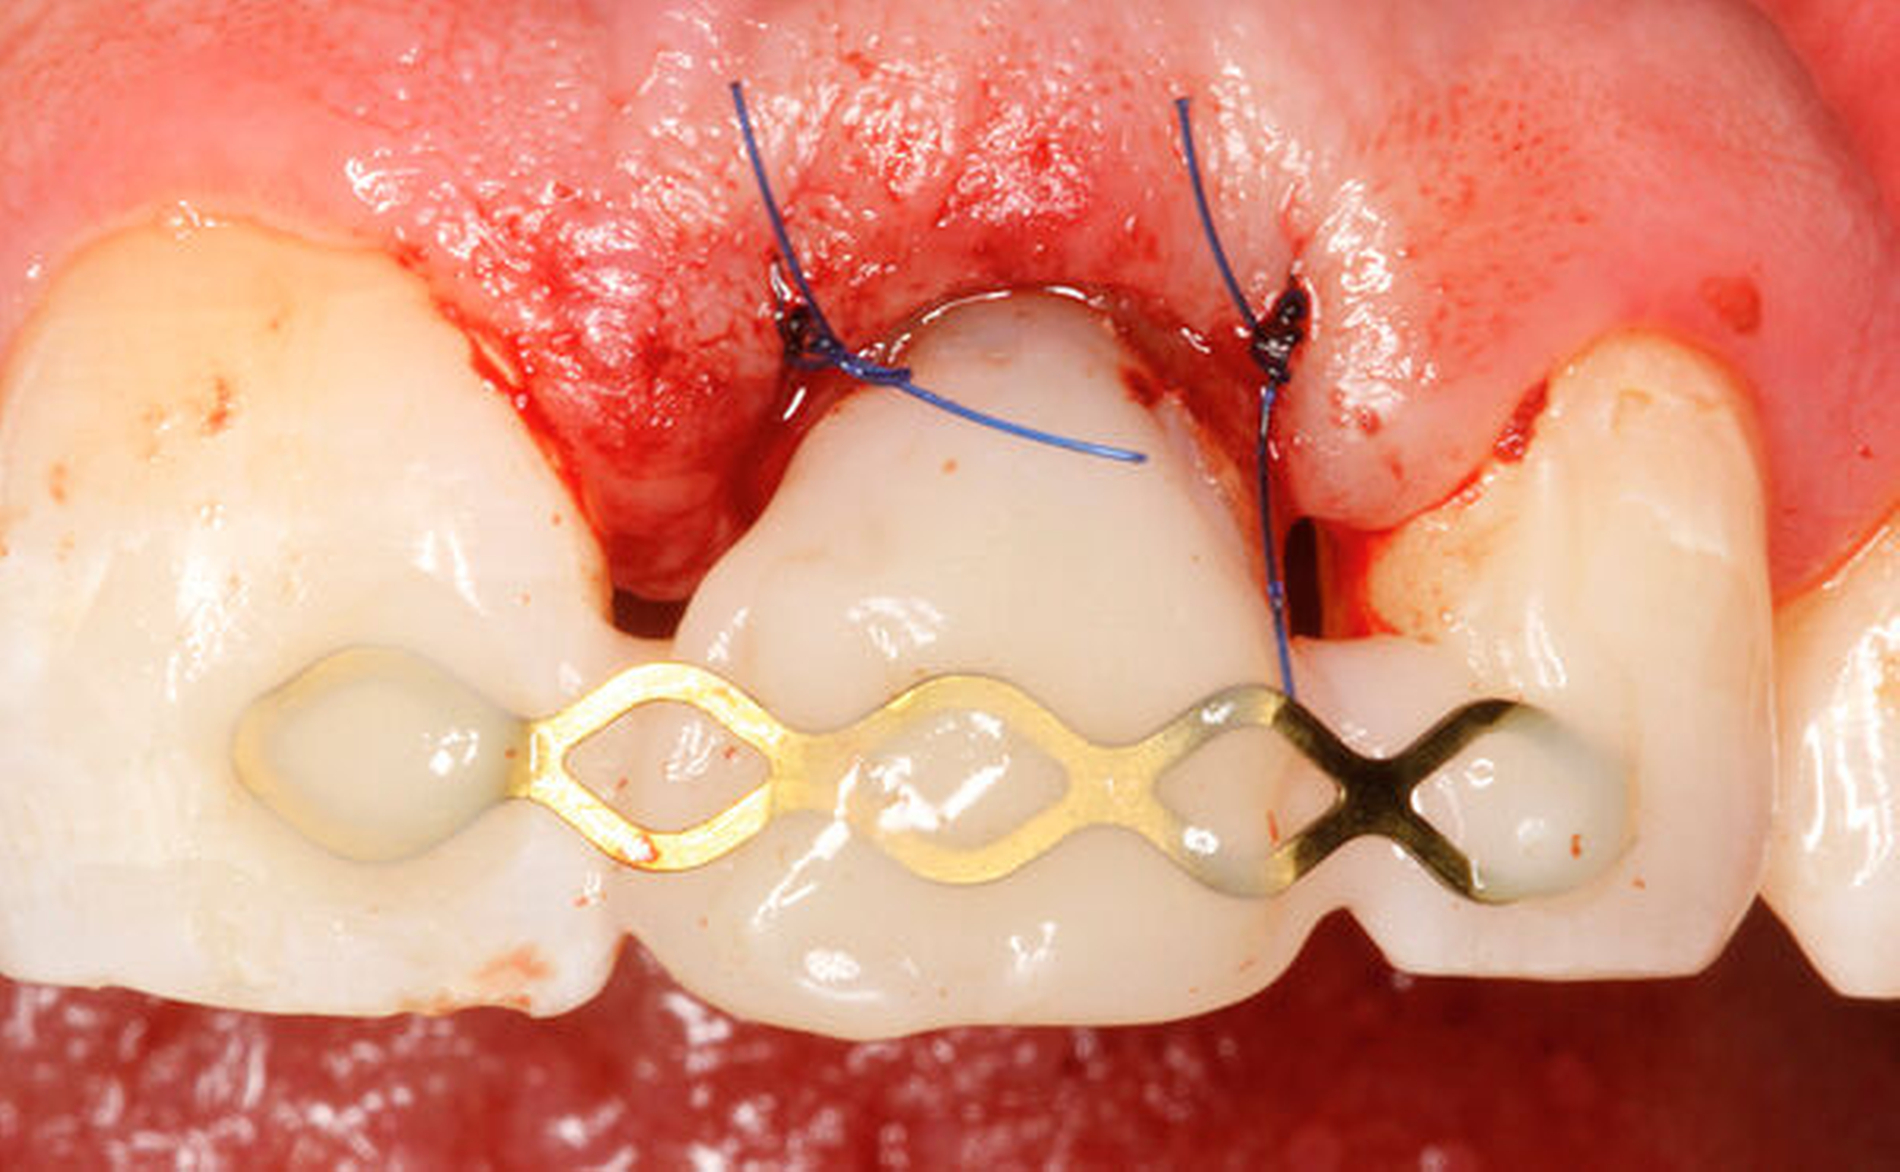

Eine weitere Möglichkeit, tief zerstörte Zähne möglichst schonend chirurgisch zu extrudieren, basiert auf axialen Zugsystemen (Abbildungen 2 bis 4). Diese erscheinen vorteilhaft bei sehr schwierigen Fällen, zum Beispiel bei Zähnen mit fehlendem Ansatzpunkt für die Zange sowie bei langen oder sehr ovalen Wurzeln. Axiale Zugsysteme ermöglichen die Übertragung von Zugkräften auf die Zahnwurzel, ohne die Alveole unnötig zu dehnen. Dazu wird eine spezielle Schraube in den Wurzelkanal eingebracht und das Gewinde der Schraube für eine ausreichende Friktion fingerfest eingedreht. An diese Schraube wird ein gerätespezifisches Zugsystem angelegt. Durch rein axial wirkende Zugkräfte werden traumatische Effekte auf Knochen und Wurzeloberfläche während der Zahnmobilisation minimiert. Gegebenenfalls können feine Luxatoren vorsichtig unterstützend eingesetzt werden. Im Tiermodell wurde an extrahierten und wieder replantierten Zähnen mit ovalem Querschnitt gezeigt, dass der Verlust von Zementoblasten auf der Wurzeloberfläche geringer ist, wenn ein axiales Zugsystem anstatt einer Extraktionszange verwendet wird.

Als Vorteil der chirurgischen Extrusion im Vergleich zur chirurgischen Kronenverlängerung wird das deutlich vorteilhaftere ästhetische Resultat mit Erhalt von Weichgewebe und Papille angegeben [Llaquet et al., 2021]. Diese Gewebe werden geschont und erfahren keine Traumata, wie dies bei einer chirurgischen Kronenverlängerung unvermeidbar geschieht [Behring et al., 2017; Lanning et al., 2003]. Indiziert ist die Extrusion vor allem bei einwurzeligen Zähnen in ästhetisch relevanten Bereichen. Biologisch betrachtet liegen solide und langzeitstabile Resultate zu dieser Technik vor. Einer aktuellen Übersichtsarbeit zufolge, basierend auf elf klinischen Studien, kann ein Behandlungserfolg mit parodontaler Heilung der Wurzel in 95 bis 100 Prozent der Fälle nach chirurgischer Extrusion erwartet werden [Plotino et al., 2020]. Eine weitere Übersichtsarbeit fokussiert auf die Häufigkeit von Komplikationen nach chirurgischer Extrusion. Den verfügbaren Daten zufolge liegt das Risiko für Zahnverlust bei fünf Prozent, das für progressive Wurzelresorptionen bei drei Prozent. Ein marginaler Knochenabbau ist ebenfalls eine seltene Komplikation (weniger als vier Prozent der Fälle). Nicht progressive Wurzelresorptionen werden mit circa 30 Prozent zwar recht häufig beobachtet, diese sind allerdings selbstlimitierend und gefährden nicht den Zahnerhalt [Elkhadem et al., 2014].